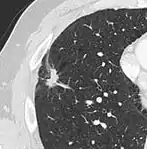

Spiculated lung nodule.[9]

- Margin morphology: a spiculated margin is a risk factor for cancer.[8] Benign causes tend to have a well defined border, whereas lobulated lesions or those with an irregular margin extending into the neighbouring tissue tend to be malignant.[10] In particular, spiculations are highly predictive of malignancy with a positive predictive value up to 90%.[9] Also, a "notch sign", which is an abrupt indentation of the nodule, increases the risk of cancer, but may also be found in granulomatous diseases.[9]